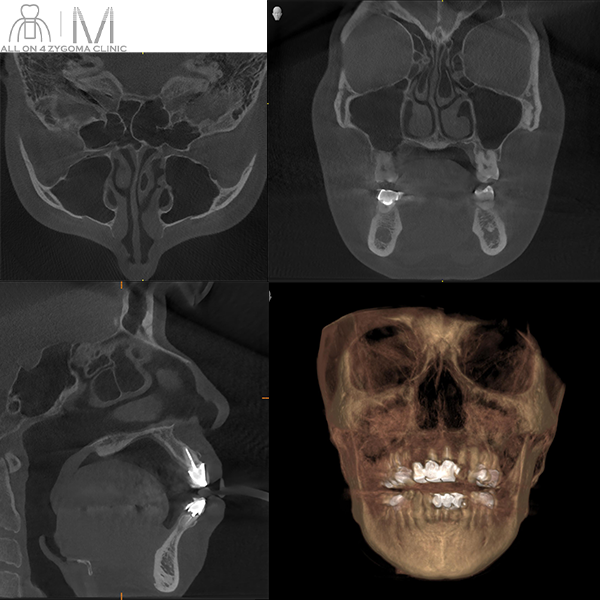

術前CT画像所見

上顎前歯部~臼歯部の頬側歯槽骨は著明な吸収像を呈しており骨が菲薄化している。両側頬骨はやや菲薄ではあるが骨幅は一応認められる。 両側上顎洞に上顎洞炎を示唆する明らかな所見は認めない。

歯槽骨の頬舌方向のボリュームが少なくノーマルインプラントの埋入が困難である事が示唆された。前歯部と臼歯部で歯槽堤の高低差が大きいことから、安定度を高めるプラットフォームの設計が必要であると考えた。また、頬骨に十分な厚みがある事からザイゴマインプラント4本を用いるオールオン4ザイゴマインプラント治療 (EZ4) を計画した。手術を円滑なものとする為、術中は静脈内鎮静法下での手術を予定した。